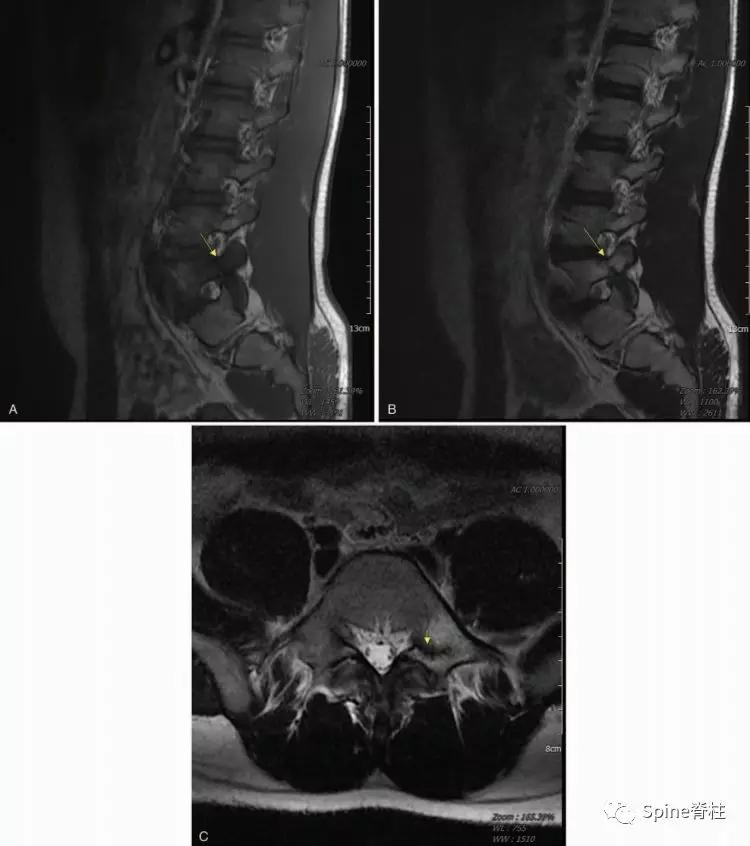

图:15岁腰痛男孩,左侧腰5椎弓根裂

A:T1左侧腰5椎弓根低信号(箭头);B:T2左侧腰5椎弓根高信号(箭头);C:T2轴位左侧腰5椎弓根骨折线明显,伴高信号区(箭头)。